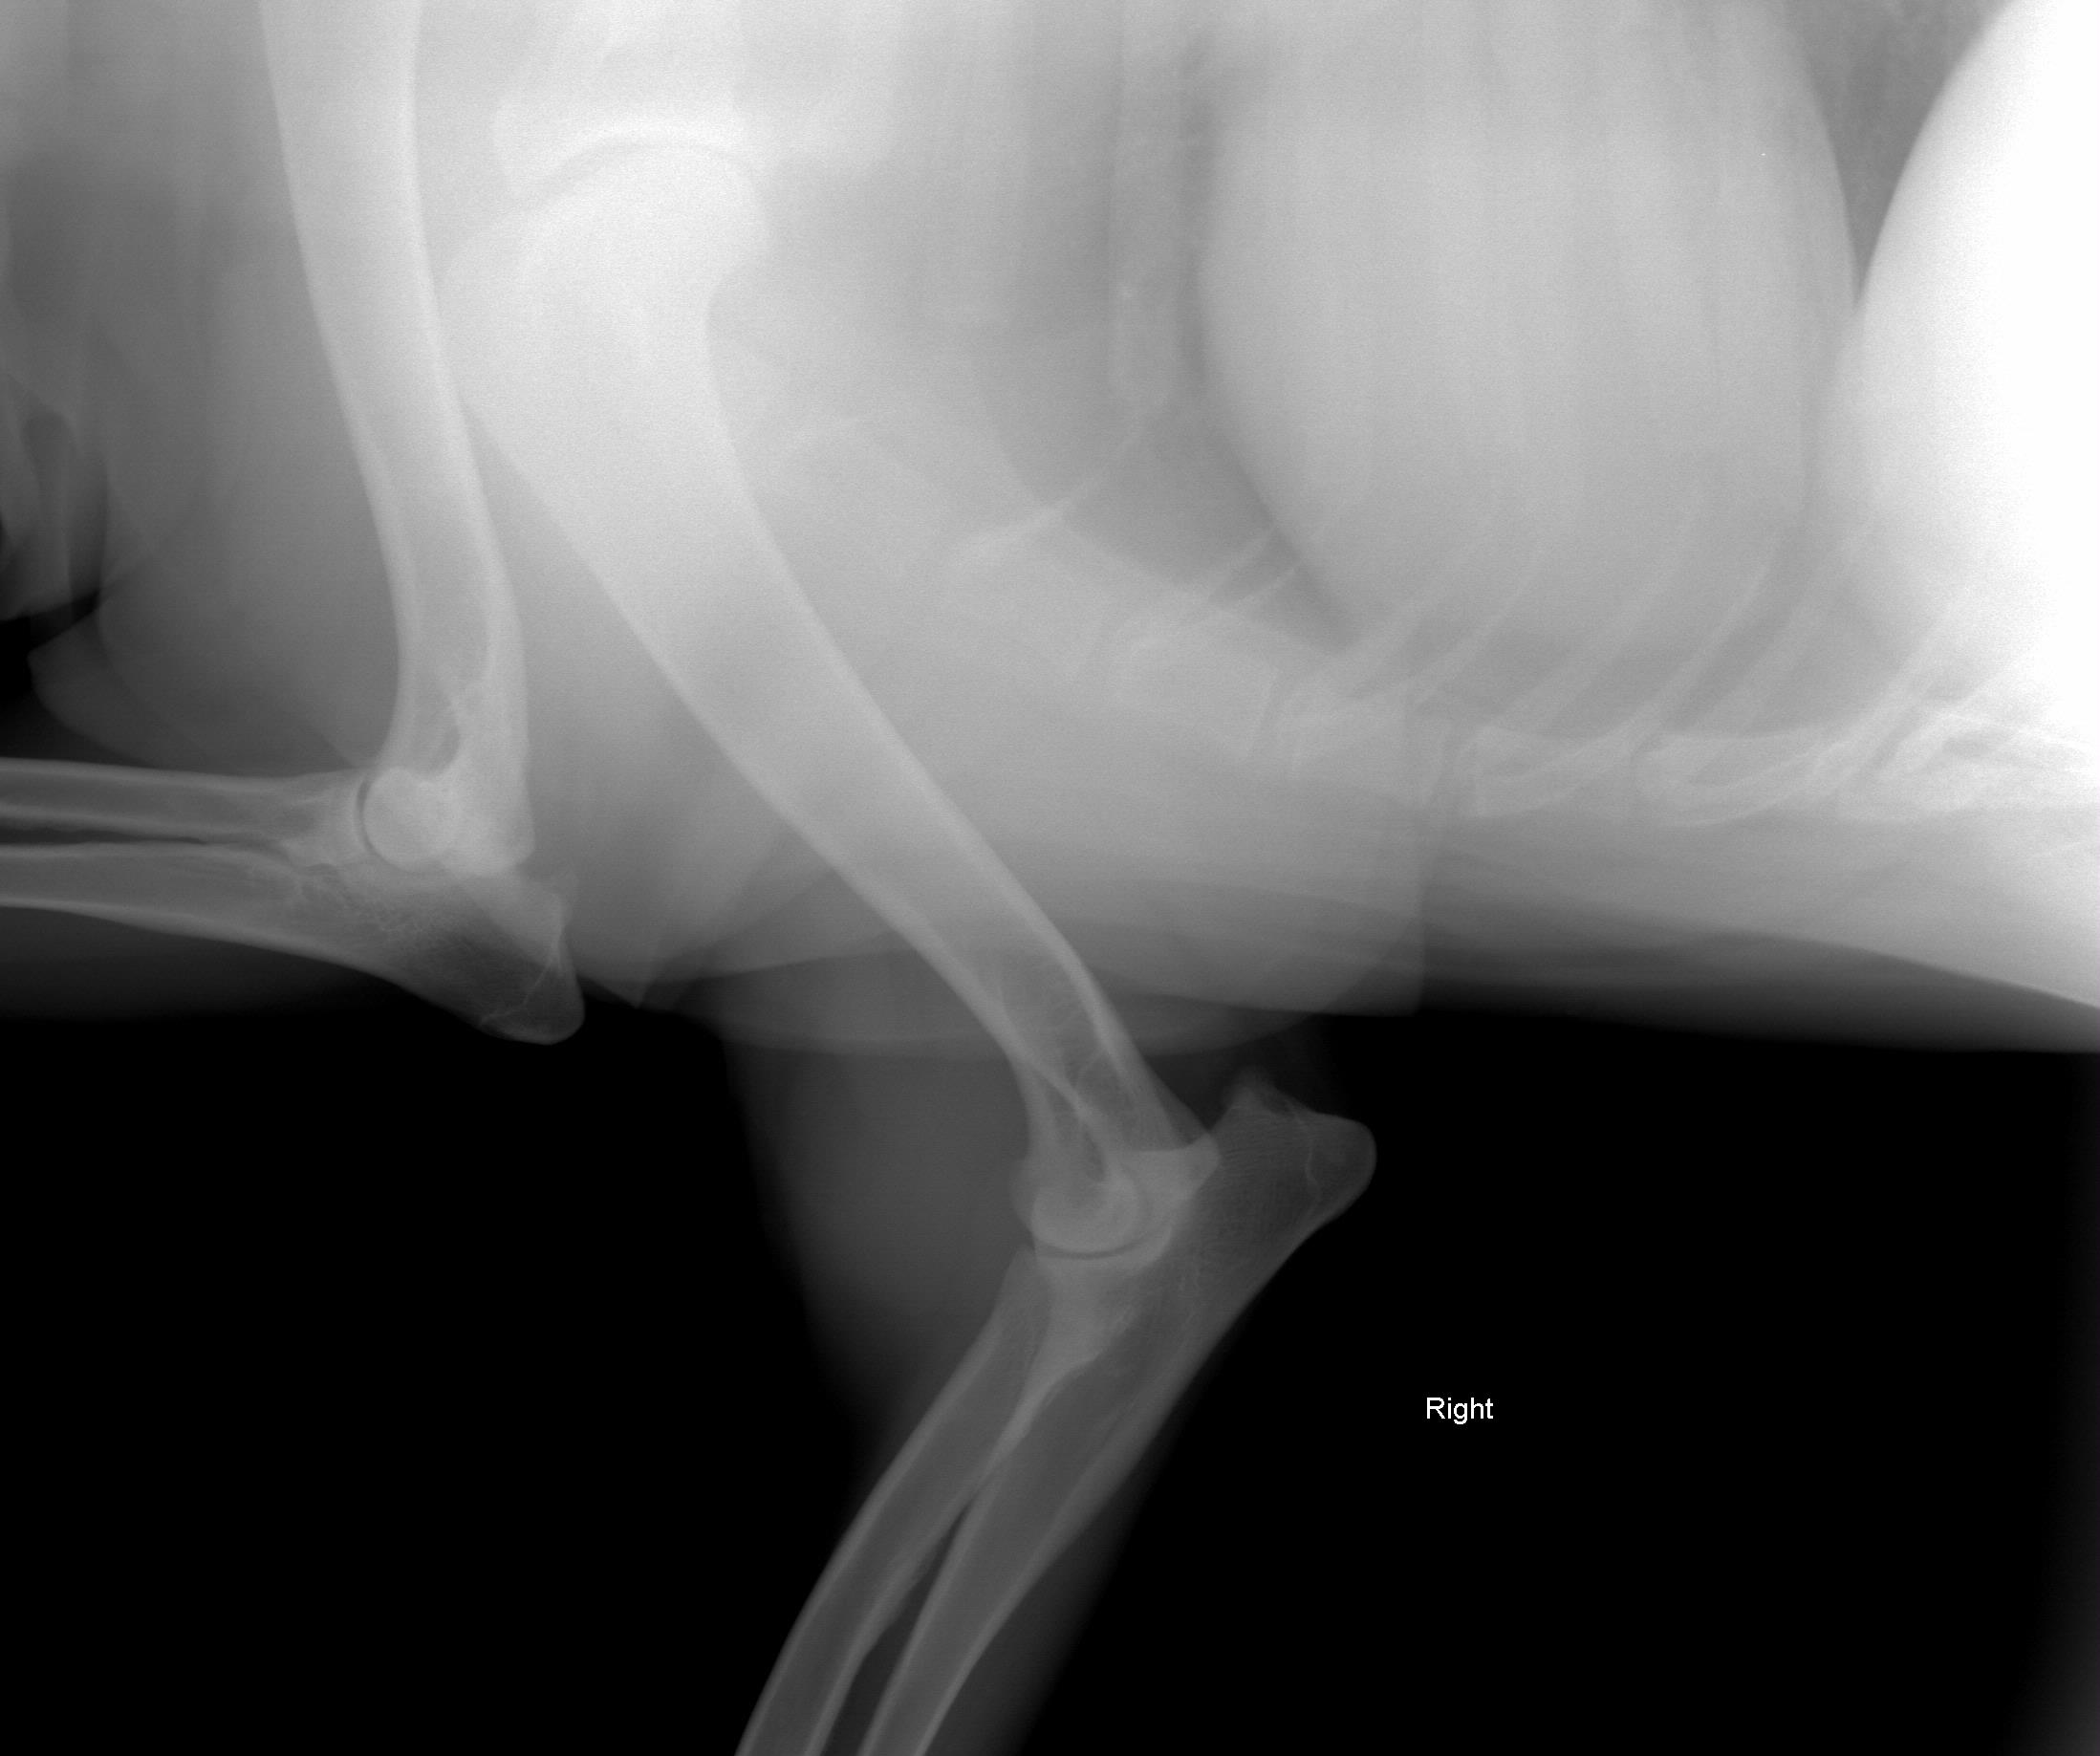

August 1, 2008 - X-rays taken at AMVC in Audubon, IA by Dr. Kristin Longfellow. She was not sedated for the x-rays. She was in slight discomfort in the area of the elbow if pressure was applied, at times seeing her trying to put weight on her toes, she was not in distress, but stiff and sore. We increased her metacam up to her weight limit.

August 4, 2008, Zoey was miserable, reluctance to go down two steps; favoring her front leg; licking it; swelling around elbow; very limited movement, etc. The swelling on the right elbow is not warm, nor cold to touch (unchanged). The swelling is hard/solid. Zoey was sleeping on her blanket (orthoped bed) on the floor without attempting to get on the bed with us at night. Zoey's eyes said she was miserable even though she was trying not to show it. The right leg is clearly marked on the xrays. She was conscious and not sedated for the xrays.

Zoey seen August 1, 2008 by Dr. Kristin Longfellow

due to limping and swelling of the front right forearm/elbow/shoulder area.

X-rays below.

On July 3, 2008, after Zoey finished her pig ear she was chasing her tail and caught the corner of the wall and never recovered from her injuries.The xray was taken 2/13/09

The following xrays were taken August 2008.